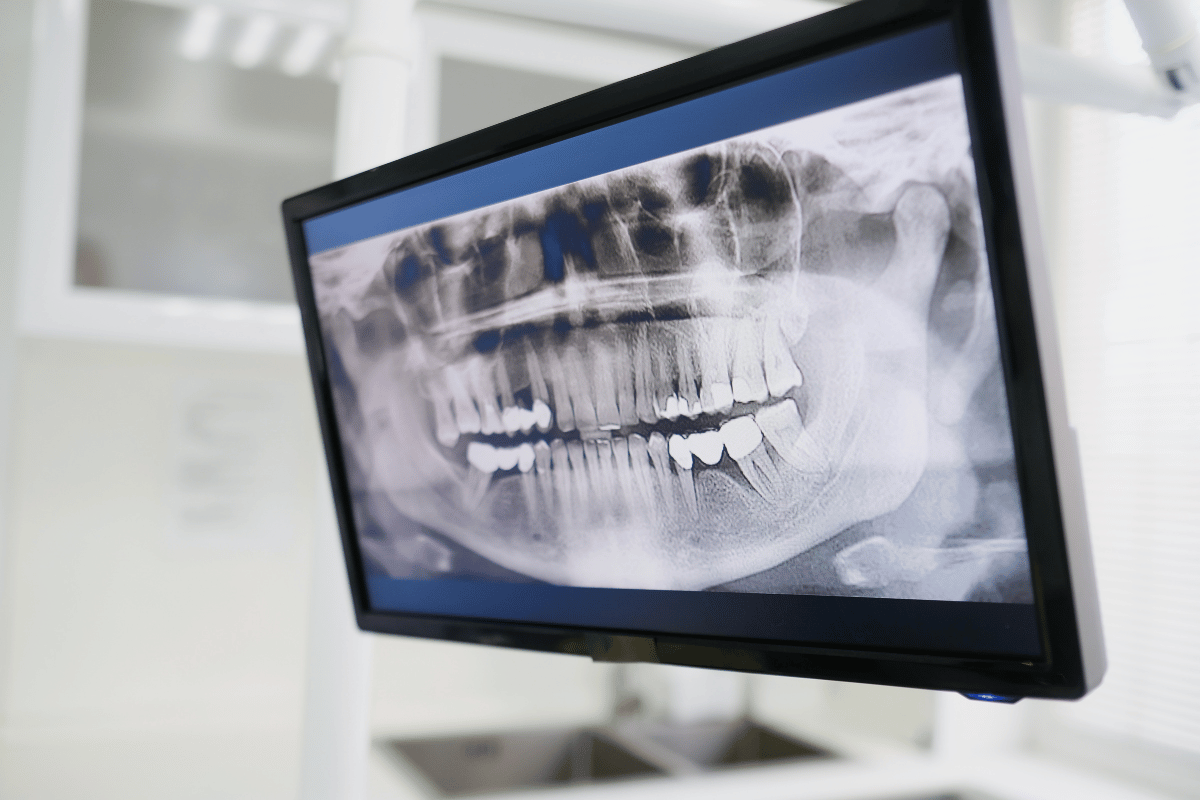

۲. تصویربرداری CBCT و تشخیص پوسیدگی پنهان

بسیاری از مشکلات دندانی (مثل کیستهای انتهای ریشه یا تحلیل استخوان) در عکسهای معمولی (OPG) دیده نمیشوند. دستگاه CBCT موجود در کلینیکهای پیشرفته، نمایی سه بعدی از استخوان فک و ریشهها به پزشک میدهد. این یعنی پزشک قبل از اینکه حتی دست به ابزار ببرد، دقیقاً میداند زیر لثه چه خبر است.